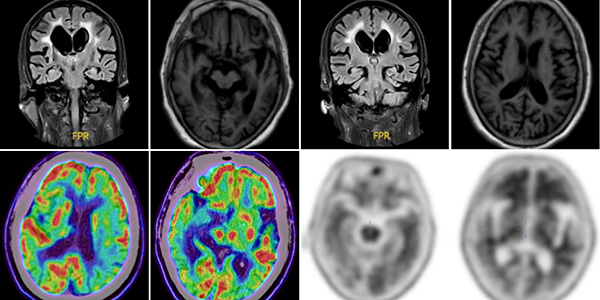

为明确诊断,痴呆与认知障碍亚专业医护人员依托人工智能辅助神经心理评估平台,对患者认知功能进行系统量化评估,结合认知谱系分析提示,患者呈现以情景记忆损害为主的海马型认知障碍模式。在排除代谢、感染、免疫及内分泌等继发性因素后,团队为患者进一步完善影像学评估,颅脑MRI提示双侧海马及颞叶萎缩;FDG-PET/CT显示双侧颞顶叶及后扣带回葡萄糖代谢减低,符合典型阿尔茨海默病代谢模式;Aβ-PET/CT检查则发现脑内弥漫性淀粉样蛋白沉积。

通过神经心理评估与多模态分子影像的整合分析,该病例完成了从临床症状到病理生物学证据支持的完整诊断链路,严格符合当前阿尔茨海默病生物标志物导向框架,最终被明确诊断为阿尔茨海默病(轻度阶段)。